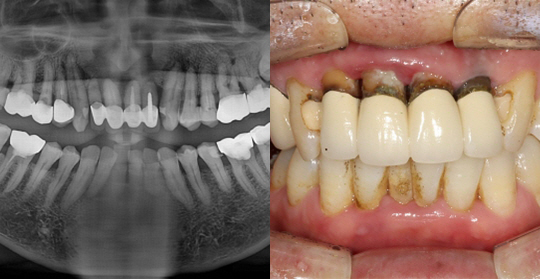

(61세 남 환자)